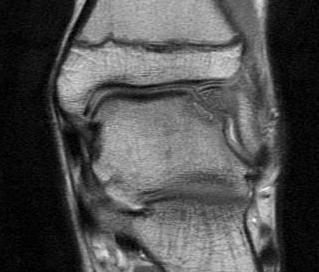

MRI

Stable lesion (Stage I) - cartilage intact, no synovial fluid under lesion

Unstable lesions (Stage II or III) - cartilage breach, synovial fluid under lesion

Displaced lesion with resultant osteochondral defect

Stable lesion with intact cartilage and no synovial fluid under lesion

Stage III completely detached but not displaced